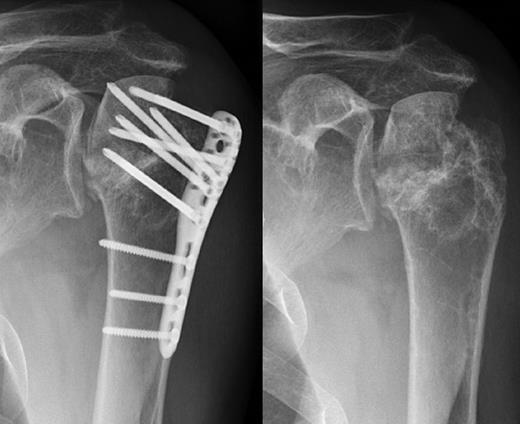

A 48-year-old patient was referred to a level I trauma center after the first incidence of an epileptic convulsion. The patient was alert and oriented with retrograde amnesia from the time of convulsion. Peripheral neurology was normal. The X-rays showed bilateral posterior shoulder dislocation with fractures of both humeral heads (Fig. 1). A CT of the head and both shoulders was performed to exclude intracerebral pathology and to achieve better demonstration of the shoulder fractures (Fig. 2). According to the AO fracture classification, he had a 11-C3.1 fracture on the left side and a 11-C3.3 fracture on the right side. The right side fracture was treated with a cementless hemiarthroplasty (OrTra®, Zimmer, Germany), while an open reduction and internal fixation (ORIF) with an angular stable plate (Philos®, Synthes, Germany) was performed on the left. Despite the high incidence for humeral head necrosis after ORIF in this fracture type, this option was chosen based on the young age of the patient. Postoperative X-rays and CT showed adequate positions of the implants (Fig. 3). The shoulders were immobilized in Gilchrist bandages followed by passive mobilization for the first 6 weeks by physiotherapy with a limitation for abduction and anteversion to 90°. There were no complications intraoperatively or in the first postoperative time. Patient was discharged after 8 days. Antiepileptic therapy was initiated with 5 mg clobazam and subsequent increasing doses over the following weeks. There were no more signs of epilepsy in the follow-up. A CT 4 months after operation showed dislocation of a fragment on the left side which was subsequently resected. At the 1-year postoperative review, the patient showed impingement of the left shoulder with abduction limited to 50° by both the plate and an osteophyte. Radiological assessment revealed signs of necrosis of the head. The plate was removed and the osteophyte resected. Eighteen months after injury, the left shoulder showed progressive avascular osetonecrosis of the head (Fig. 4) and after plate removal an inversed prosthetic replacement had to be performed (Fig. 5). At the last follow-up 3 years after injury, the patient was free of pain with a bilateral range of motion of 90° abduction and elevation.

Postoperative X-rays after hemiprothetic replacement on the right and angle stable plate osteosynthesis on the left side.